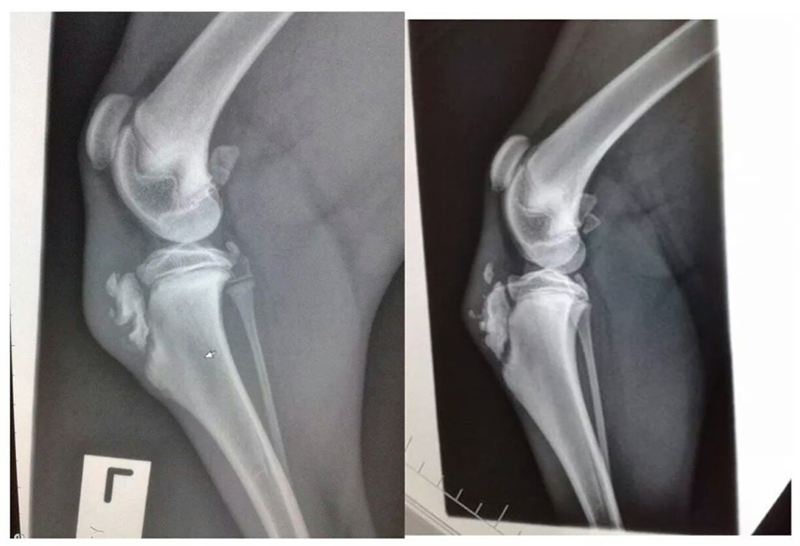

Please look below at all these x-rays from last years random friend’s injuries ( and these are without even searching as these happen all the time). If it is not a growth plate , it is a neck, back, wrist, hock, ribs or any large bones for that matter. One of the most common example is when a small piece of the knee joint splits, which end up in a 2-3000€ surgery. I do not see much point in taking such a huge risk, so don’t run adults and pups! Period!

Here is the proof! More info after the pictures!

• The diagrams below show the different type of fractures (the blue line represents the soft growth plate tissue, the red line represents the fracture line, and the speckled red line is a crushed growth plate).

Common locations of the various Salter-Harris growth plate fractures in dogs and cats • Type1 – hip joint (slipped femoral capitis), knee (distal femur)

• Type 2 – knee (distal femur)

• Type 3 – elbow (distal humerus)

• Type 4 – elbow (distal humerus)

• Type 5 – 1. wrist or carpus (distal ulna or the distal radius less commonly), this results in an angular limb deformity); 2. ankle or hock (distal tibia)